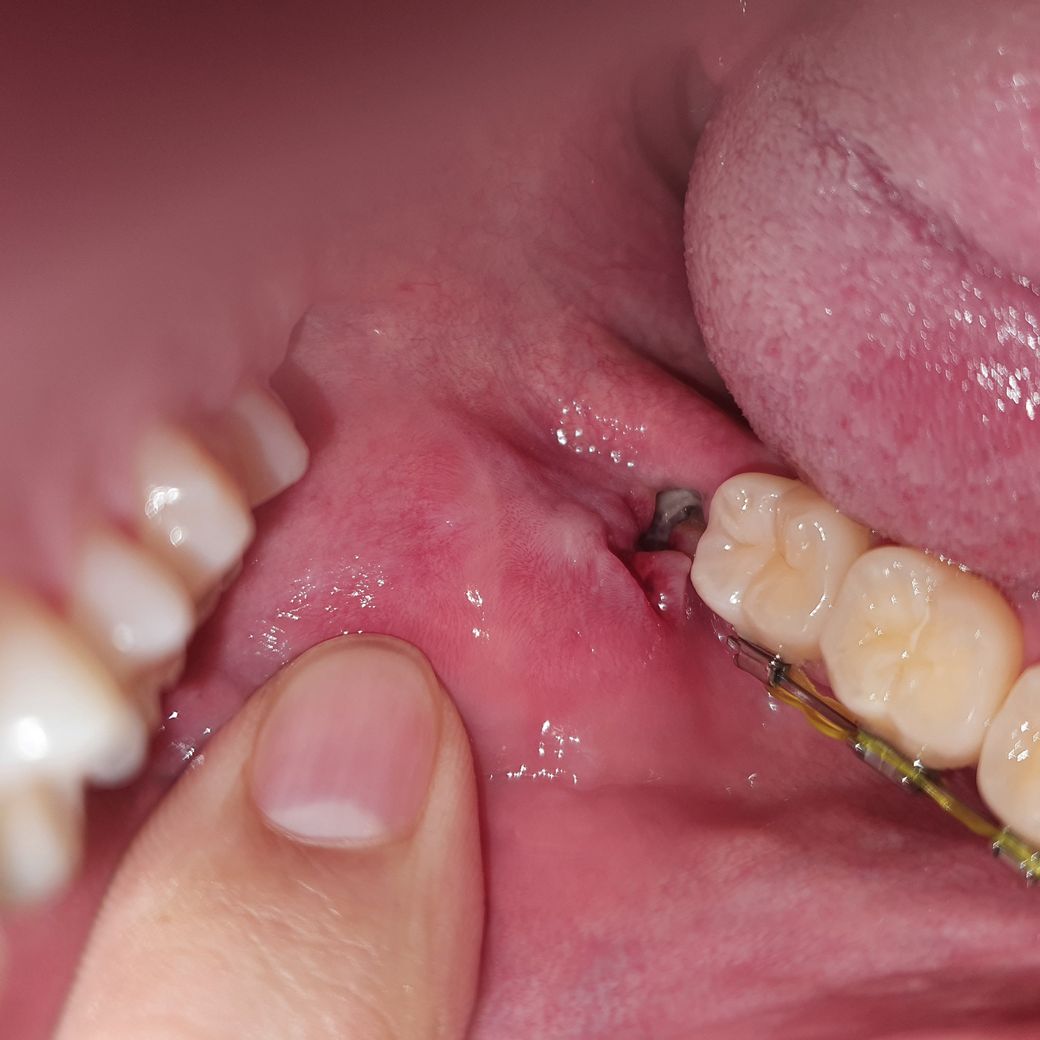

사랑니 발치 했는데 치조골 인가요??

하악 사랑니를 발치한지 일주일 정도 지났는데 안쪽에 하얀게 있어요!

치조골이 맞나요??

아니라면 무엇인가요??

실밥 제거한 날 찍은 사진인데 가만히 두면 아물겠죠?

만약 안에 음식물이 들어가면 자연히 빠지겠죠?

• 1번 째 사진

일부 치조골과 정상적으로 회복되고 있는 섬유 조직 및 육아조직으로 보입니다. 즉 우리 회복되는 과정에서 보이는 정상적인 반응이며 실밥은 다로 보이지 않습니다. 또한 현재 주변 부위 염증이 관찰되지 않고 붓기도 없는 것으로 보아 정상적으로 회복되고 있는 것으로 판단됩니다. 크게 걱정하지 않으셔도 되며 시간이 지나면 자연스럽게 잇몸이 회복되고 닫힐 것입니다.

사진으로 봤을 때 음식물이 오래되어 생긴 치태나 찌거기 또는 혈병의 일종일 수 있습니다.

또는, 말씀하신대로 치조골이 노출된 것일 수 도 있지만, 통증이 없다면 보통 가능성이 낮습니다.

사랑니 발치한 자리에 흰색이 보여서 걱정되셨군요.

발치 후 dry socket이 아니라면 치조골이 저렇게 하얗게 노출되어 있지 않기 때문에 그냥 음식물이 들어간 것 같습니다.

음식물이 들어가면 저절로 빠질 수 있고 시간이 지나면 잇몸이 닫혀서 잘 아물겠지만 물로 헹궈주시거나 따뜻한 생리식염수로 헹궈주시면 좋습니다.